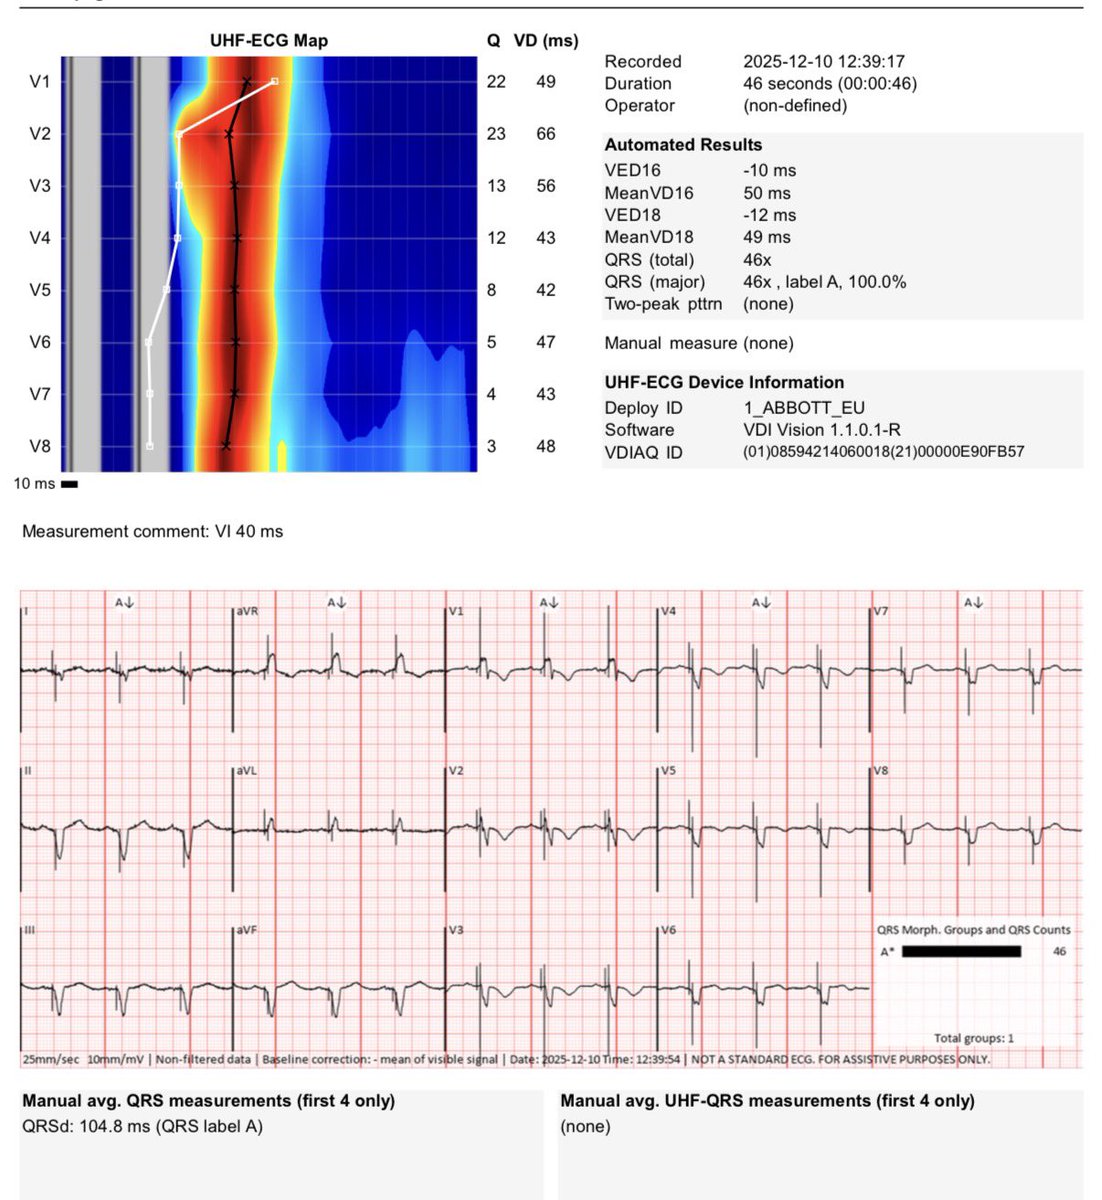

Upgrade from an DDD ICD to CRT-D #Abbott in a patient with ischemic cardiomyopathy and 100% RV stimulation. Initial QRS 200ms, final 104 ms. Hospital Dr. Jose Molina Orosa Lanzarote @ArritmiasJMO #Cardiology